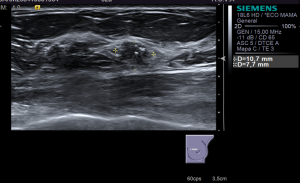

La ecografía es el método de imagen más utilizado en la mama, después de la mamografía. Permite la evaluación y caracterización de nódulos mamarios detectados en mamografía, ayudando a diferenciar lesiones benignas de malignas.